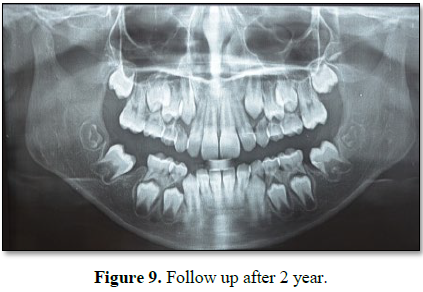

After 2 years of follow up, the 37 and 47 have physiologically mesially

migrated at the site of extracted first

molars uneventfully (Figure 9).